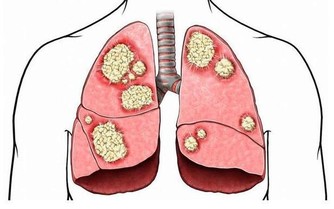

胸椎3T

供應部位:肺、氣管、胸膜;神經受壓後果:支氣管炎、肺炎、肺充血(胸膜炎)、流行性感冒